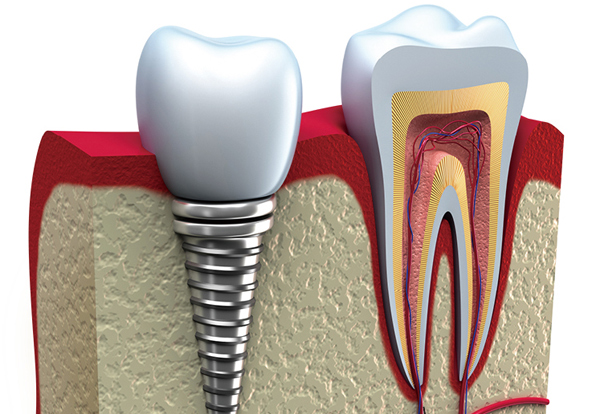

第三种是种植牙,在缺牙处的牙骨中植入纯钛种植体,在种植体上安装仿生牙冠(如下图)。这种方式模仿真牙,有固定在牙骨中的牙根部分(种植体),有负责咀嚼和美观的牙冠部分。种植牙的优点是:舒适,逼真美观咀嚼效率高,不需要磨除相邻的牙齿。缺点是:价格相对较高。

种植牙的牙冠部分有烤瓷牙和全瓷牙的选择,全瓷牙的美观度和生物相容性要优于烤瓷牙,当然价格比烤瓷牙高不少。此次苏报“种牙1+1”计划,为提前报名的种牙市民免费升级更好的种植牙,由烤瓷牙升级成全瓷牙。

▲种植牙图示